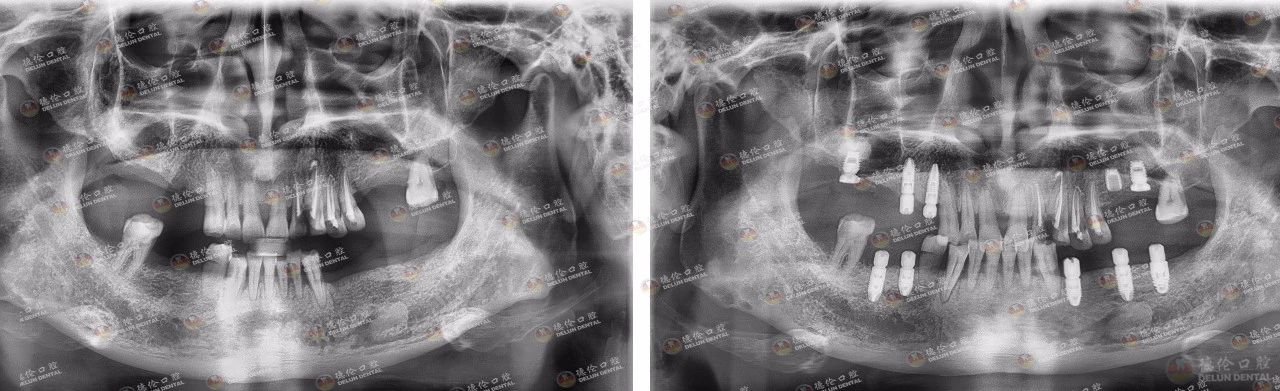

雷教授种牙前(左)后(右)对比图

经过一段时间的诊疗雷教授完成了缺牙修复,他将自己的大半生无私地奉献给祖国的教育事业、他挚爱的学生,德伦口腔用自己的专业技术让雷教授重获一口好牙,让他可以继续在三尺讲台上继续自信讲学,为国家培养更多的专业人才。